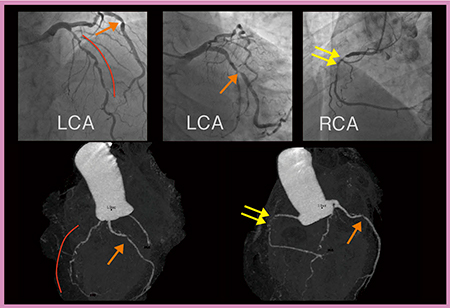

症例1は,DLP 54.4mGy・cm,実効線量0.8mSvと,1mSv以下の被ばく線量で冠動脈の非石灰化プラークが明瞭に描出されており,ナプキンリングサインと思われるハイリスクプラークの同定も可能であった(図1)。

図1 症例1:低被ばく撮影における非石灰化プラークの描出